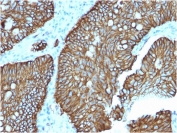

It recognizes a glycosylated protein of 120kDa, which is identified as Cadherin 17 (also known as LI Cadherin). The cadherins are a family of Calcium-dependent adhesion molecules that function to mediate cell-cell binding critical to the maintenance of tissue structure and morphogenesis. Cadherins each contain a large extracellular domain at the amino terminus, which is characterized by a series of five homologous repeats, the most distal of which is thought to be responsible for binding specificity. The relatively short carboxy terminal, intracellular domain interacts with a variety of cytoplasmic proteins, including beta-catenin, to regulate cadherin function. LI-cadherin (for liver-intestine-cadherin) expression is restricted to liver and intestine tissues and is specifically localized to the basolateral domain of hepatocytes and enterocytes.

A recombinant human partial protein (amino acids 242-418) was used as the immunogen for the Cadherin 17 antibody.